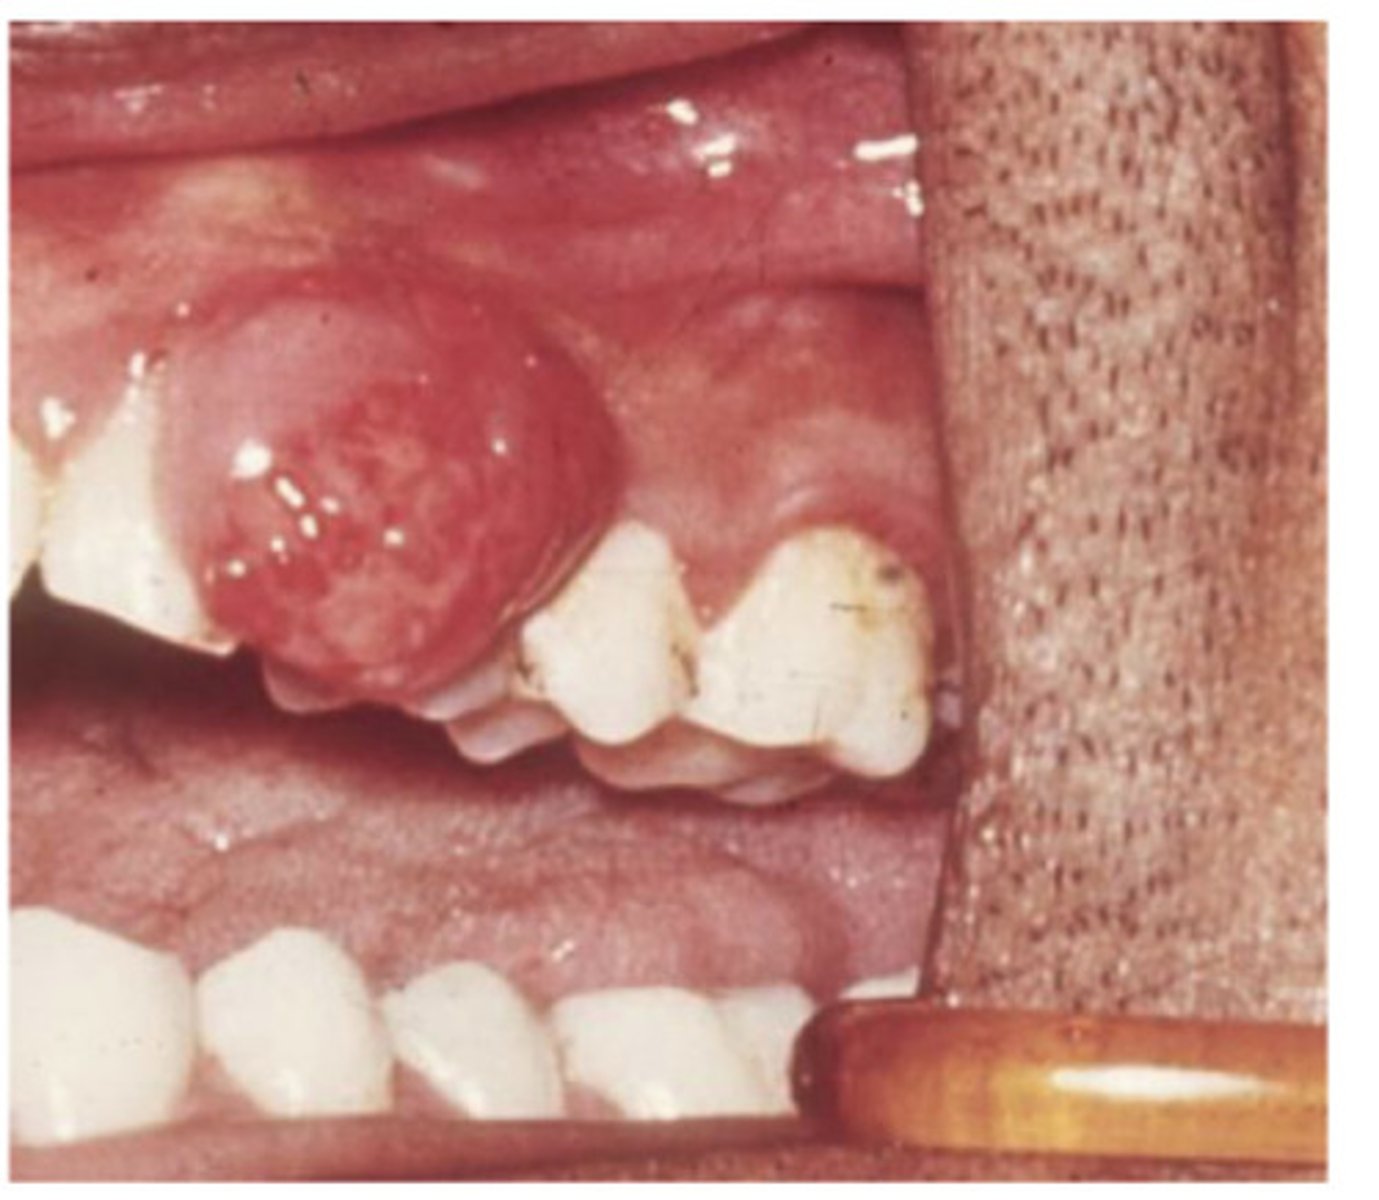

What is this?

Pregnancy epulis

Usually an over response to an irritant - can appear with or without good OH can be common in pregnancy - they are usually surgically removed